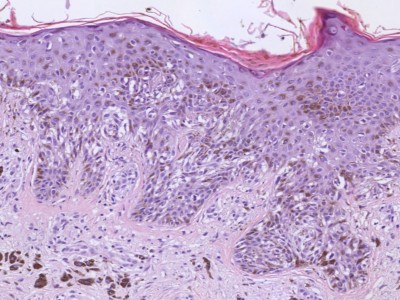

PA:In de 'precarcinomateuze' vorm is er alleen toename van het aantal melanocyten in de basale lagen, ook buiten de grenzen van de laesie, en in de basale laag van de uitwendige wortelschede van de haarfollikels. Soms zijn deze melanocyten iets atypisch vergeleken met die in normale huid. Buiten de lentigo maligna begrenzing ziet men ze apart liggen, van elkaar gescheiden door een of enkele basale cellen, maar er binnen kunnen ze vrijwel de gehele basale laag innemen, hier en daar in nestjes als het ware aan de epidermis hangend. De melanocyten kunnen zeer variëren in grootte. Naast normale melanocyten komen ook grote cellen met enkele kernen voor. De dendrieten zijn duidelijk en de pigmentatie is meestal goed ontwikkeld. Nesten van atypische melanocyten kunnen intra-epidermaal voorkomen, maar een Pagetoïde groei zoals bij het superficial spreading melanoma tot in het oppervlak van de epidermis is bij lentigo maligna ongewoon. In de cutis is er enige, meestal geringe aspecifieke ontsteking. In de infiltratieve fase (lentigo maligna melanoom) komen vaak spoelvormige, donker gepigmenteerde cellen voor in het stratum papillaire. In deze fase ziet men wel kleine tumorcelnesten, vooral bij de noduli; opvallend is het grote aantal spoelcellen. Overigens bestaat er dan veel overeenkomst met de andere melanoomvormen. In de cutis ziet men dat in dat geval veel cellen door een licht aspecifiek ontstekingsinfiltraat zijn omgeven.

![Histologie lentigo maligna melanoma (click on photo to enlarge) [source: Kevin Kwee / Afdeling Pathologie MUMC] Histologie lentigo maligna melanoma](../../../pacoupes/thumbnails/lentigo-maligna-melanoma-1.jpg) |

![Histologie lentigo maligna melanoma (click on photo to enlarge) [source: Kevin Kwee / Afdeling Pathologie MUMC] Histologie lentigo maligna melanoma](../../../pacoupes/thumbnails/lentigo-maligna-melanoma-2.jpg) |

![Histologie lentigo maligna melanoma (click on photo to enlarge) [source: Kevin Kwee / Afdeling Pathologie MUMC] Histologie lentigo maligna melanoma](../../../pacoupes/thumbnails/lentigo-maligna-melanoma-3.jpg) |

|

ingescande coupe (zoom) |